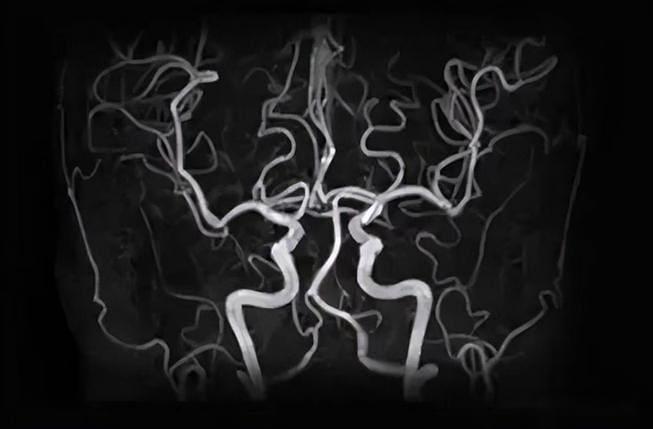

脑血管磁共振(MRA)检查

脑血管磁共振成像(MRA)采用磁共振成像技术,检查是一种微创血管成像技术。(MRI)分析血管结构的技术。由于MRI设备可以通过磁场和电磁波的相互作用来区分血液和周围组织,因此在进行MRA检查时,病人不需要注射造影剂。

相比之下,MRA检查是基于磁共振成像技术,利用磁场和射频脉冲获取血管图像,对患者来说更安全,无需造影剂和辐射。MRA特别擅长显示血管狭窄和阻塞的部位,以及动脉瘤、动脉畸形等血管疾病。